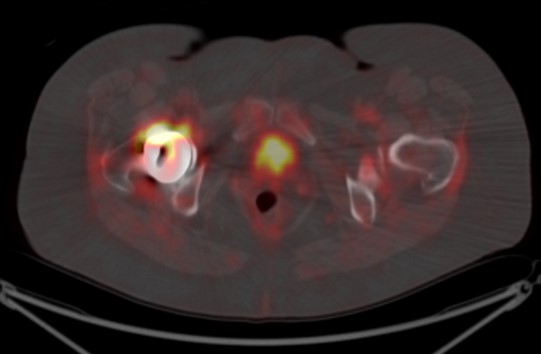

A) 50 year-old women with history of osteosarcoma of left distal femur status post resection and limb sparing prosthesis. B) Left to right, top to bottom, axial bone window CT and FDG PET, fused axial and coronal images of the lower thigh demonstrate the prosthesis within the distal left femur producing streak artifact and photopenia on the PET images. |

60 year-old women with right hip hemiarthoplasty. Axial CT bone window image (5A) demonstrates right hip prosthesis. |

| Axial bone window (5B) NON-attenuation corrected (NAC) and attenuation corrected (AC) FDG PET (5C), fused axial and coronal (5D, 5E), images of the pelvis demonstrate the right femoral prosthesis with photopenia in the region of prosthesis. Periprosthetic FDG uptake is seen on AC and fused images and is minimally seen on the NAC image, consistent with attenuation correction artifact. |